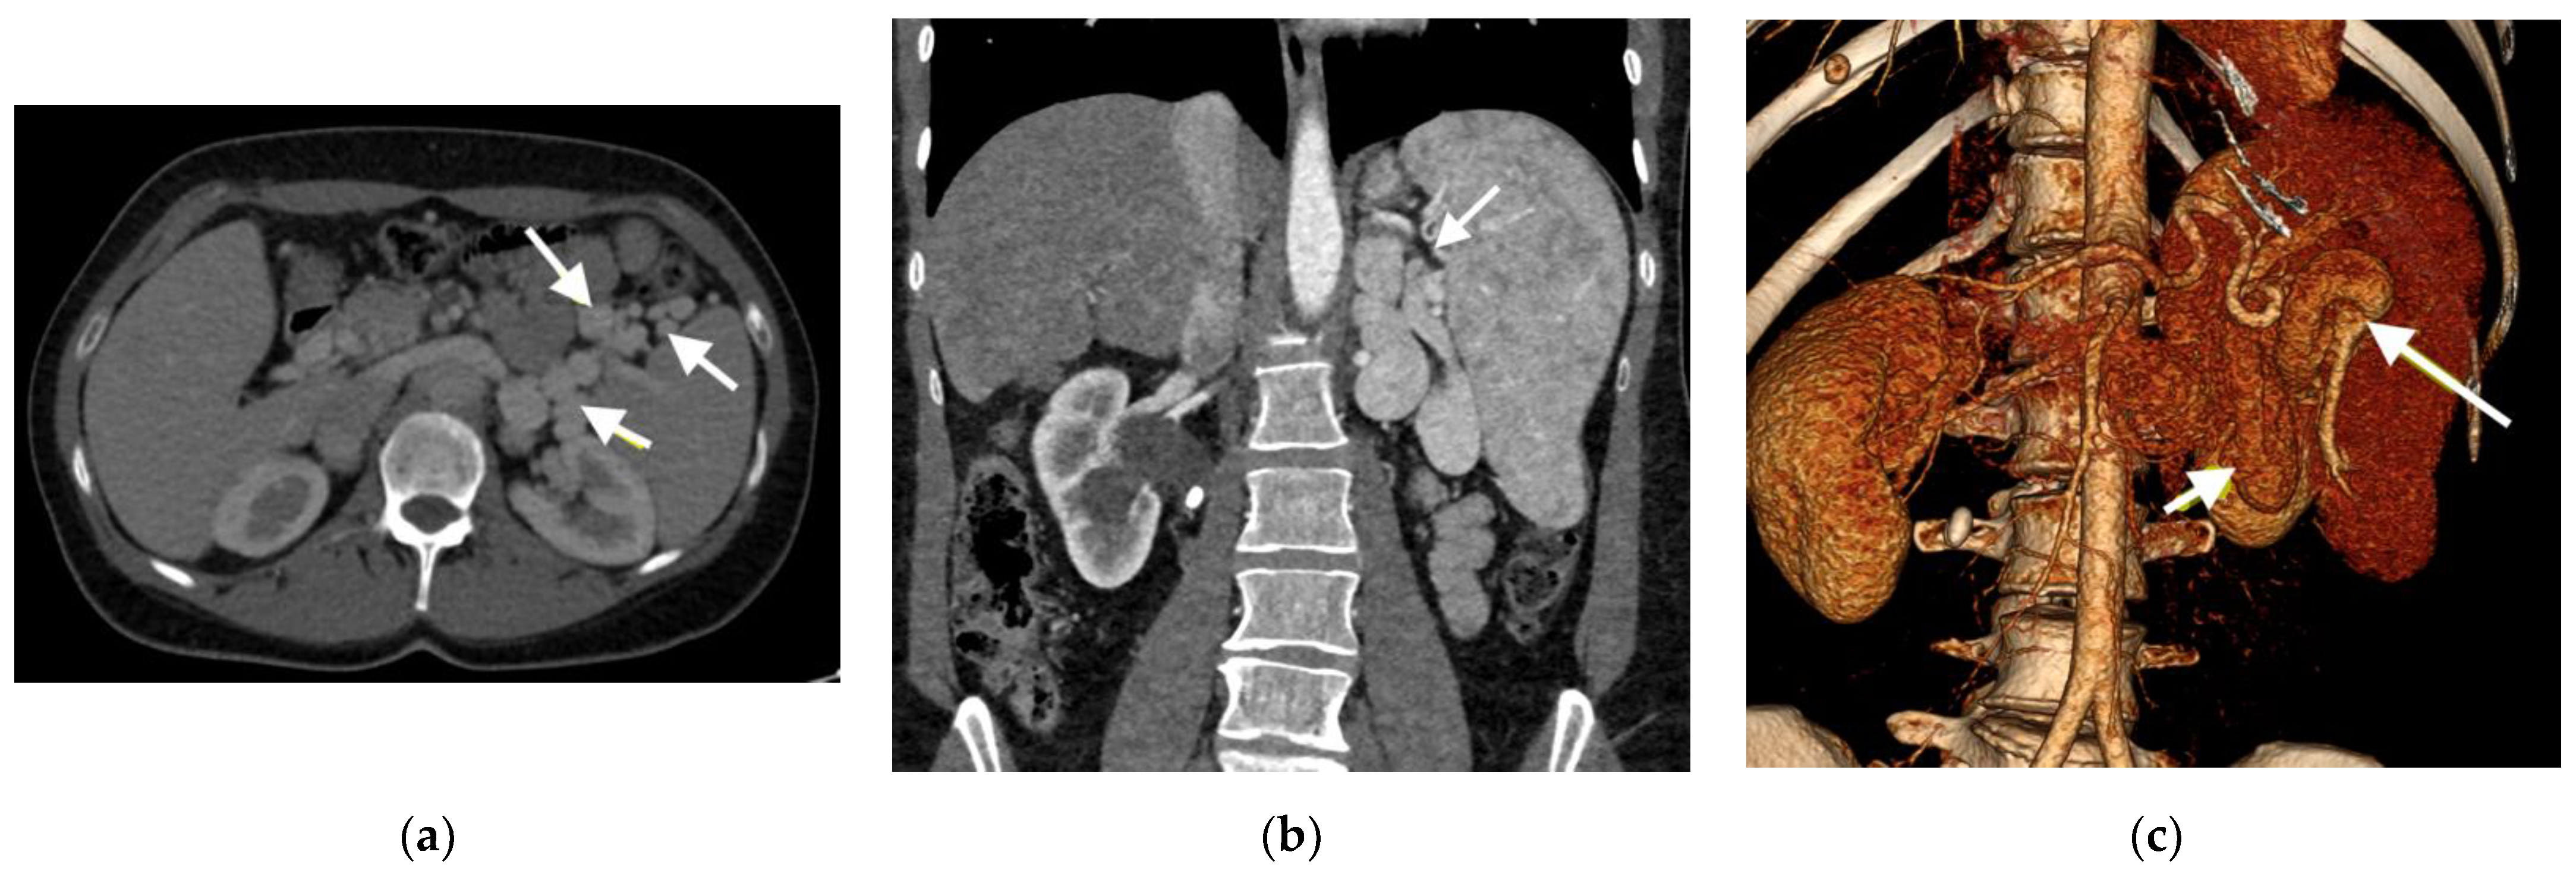

- Type I—end-to -side anastomosis with a complete portosystemic shunt exhibiting no visible portal flow in the liver due to the absence of intrahepatic portal veins. The malformation is female-predominant and associated with other congenital abnormalities, such as cardiac defects.

- Type II—side-to side-anastomosis with hypoplastic intrahepatic portal veins, and the liver is perfused with portal blood in the presence of a partial shunt (e.g., porto-hepatic venous anastomoses) [4].